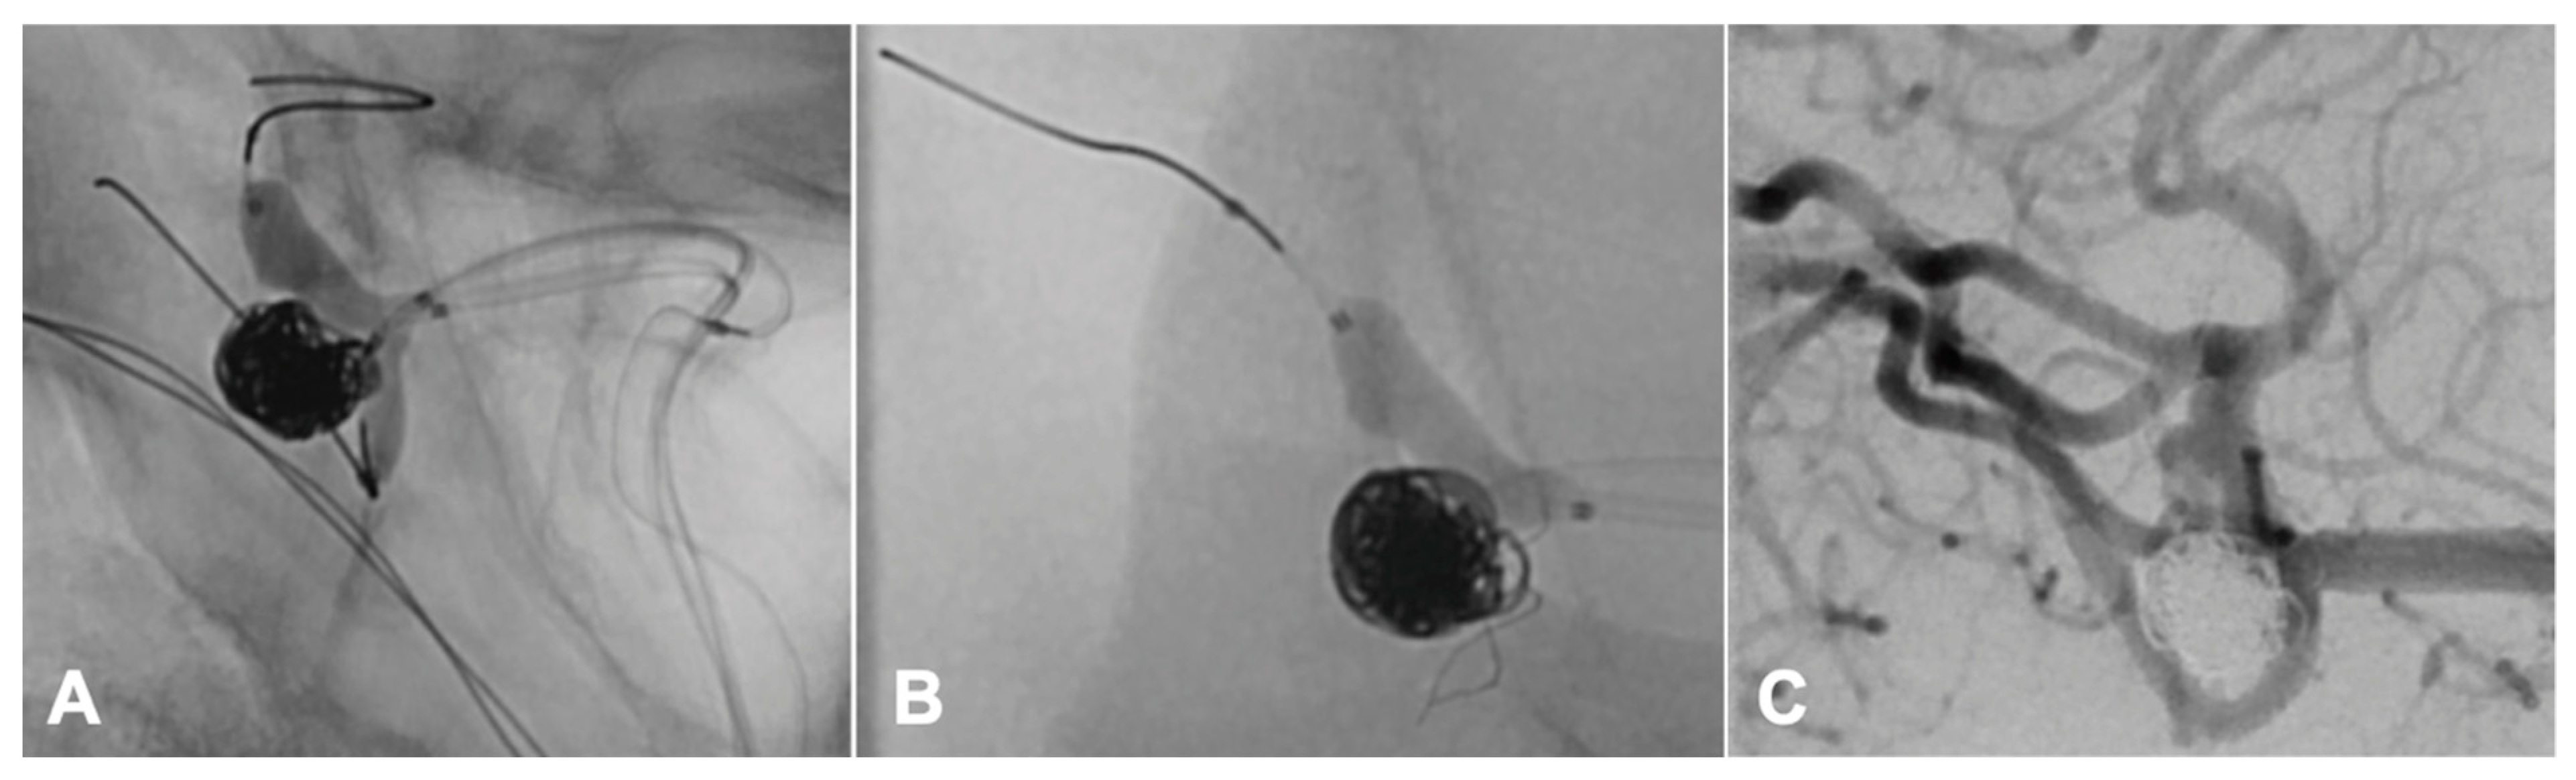

Figure 2.

Peri-interventional stroke management. Vessel occlusion due to a coil protrusion into the middle cerebral artery (M2). This coil protrusion increased during the following balloon deflation with subsequent resulting IINM changes (A). Positioning a stent through the balloon catheter for coil stabilization (B). Regular flow in the DSA control (C).

In one patient, who was treated with balloon-assisted coiling and surveilled with intra-operative neurophysiological monitoring, we detected a peri-interventional stroke with neurophysiological monitoring during the intervention (Figure 1), which we could treat immediately by placing a stent (Figure 2).

Neurophysiological monitoring is a central tool of intraoperative and intrainterventional care critical for detecting central and peripheral ischemic events. The recognition of potential changes in SSEPs/TcMEPs, which could be caused by intracranial hemorrhage or ischemic stroke, is essential in the avoidance of permanent deficits. In one cause of an intrainterventional minor stroke, we were able to detect the event first in IINM changes. Without neurophysiological monitoring, we would have detected the vascular occlusion later.